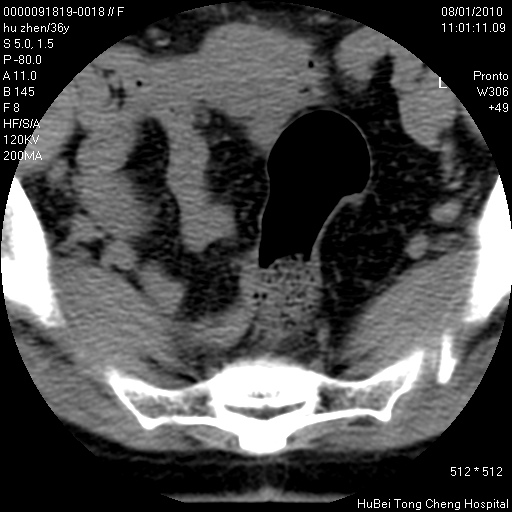

患者 女,36岁。右侧腰腿痛半月余。腰骶椎mr平扫偶然发现骶椎异常信号。

临床诊断:1)腰椎间盘突出症。2)骶椎肿瘤性病变?

骶椎ct平扫(层厚、层距均为5mm),图像如下:

考虑s1骨纤维异常增殖症。

良性骨病变,骨纤还是骨母细胞瘤?